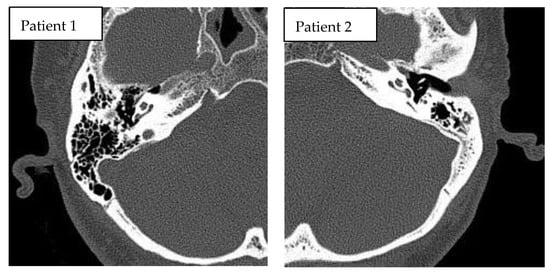

3.3. Imaging